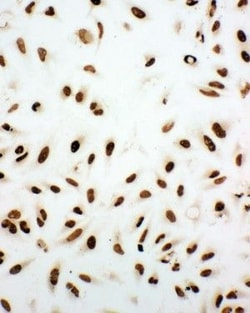

Reconstitute with 0.2 mL of distilled water to yield a concentration of 500 μg/mL. Positive Control - WB: human Hela whole cell, human A549 whole cell, human 293T whole cell, human HepG2 whole cell. IHC: human intestinal cancer tissue, human lung cancer tissue, human mammary cancer tissue, human mammary cancer tissue. ICC/IF: A549 cell, Hela cell. Flow: SiHa cell. Store at -20°C for one year from date of receipt. After reconstitution, at 4°C for one month. It can also be aliquotted and stored frozen at -20°C for six months. Avoid repeated freeze-thaw cycles.

| Flow Cytometry, Immunohistochemistry, Immunohistochemistry (Paraffin), Western Blot, Immunocytochemistry | |